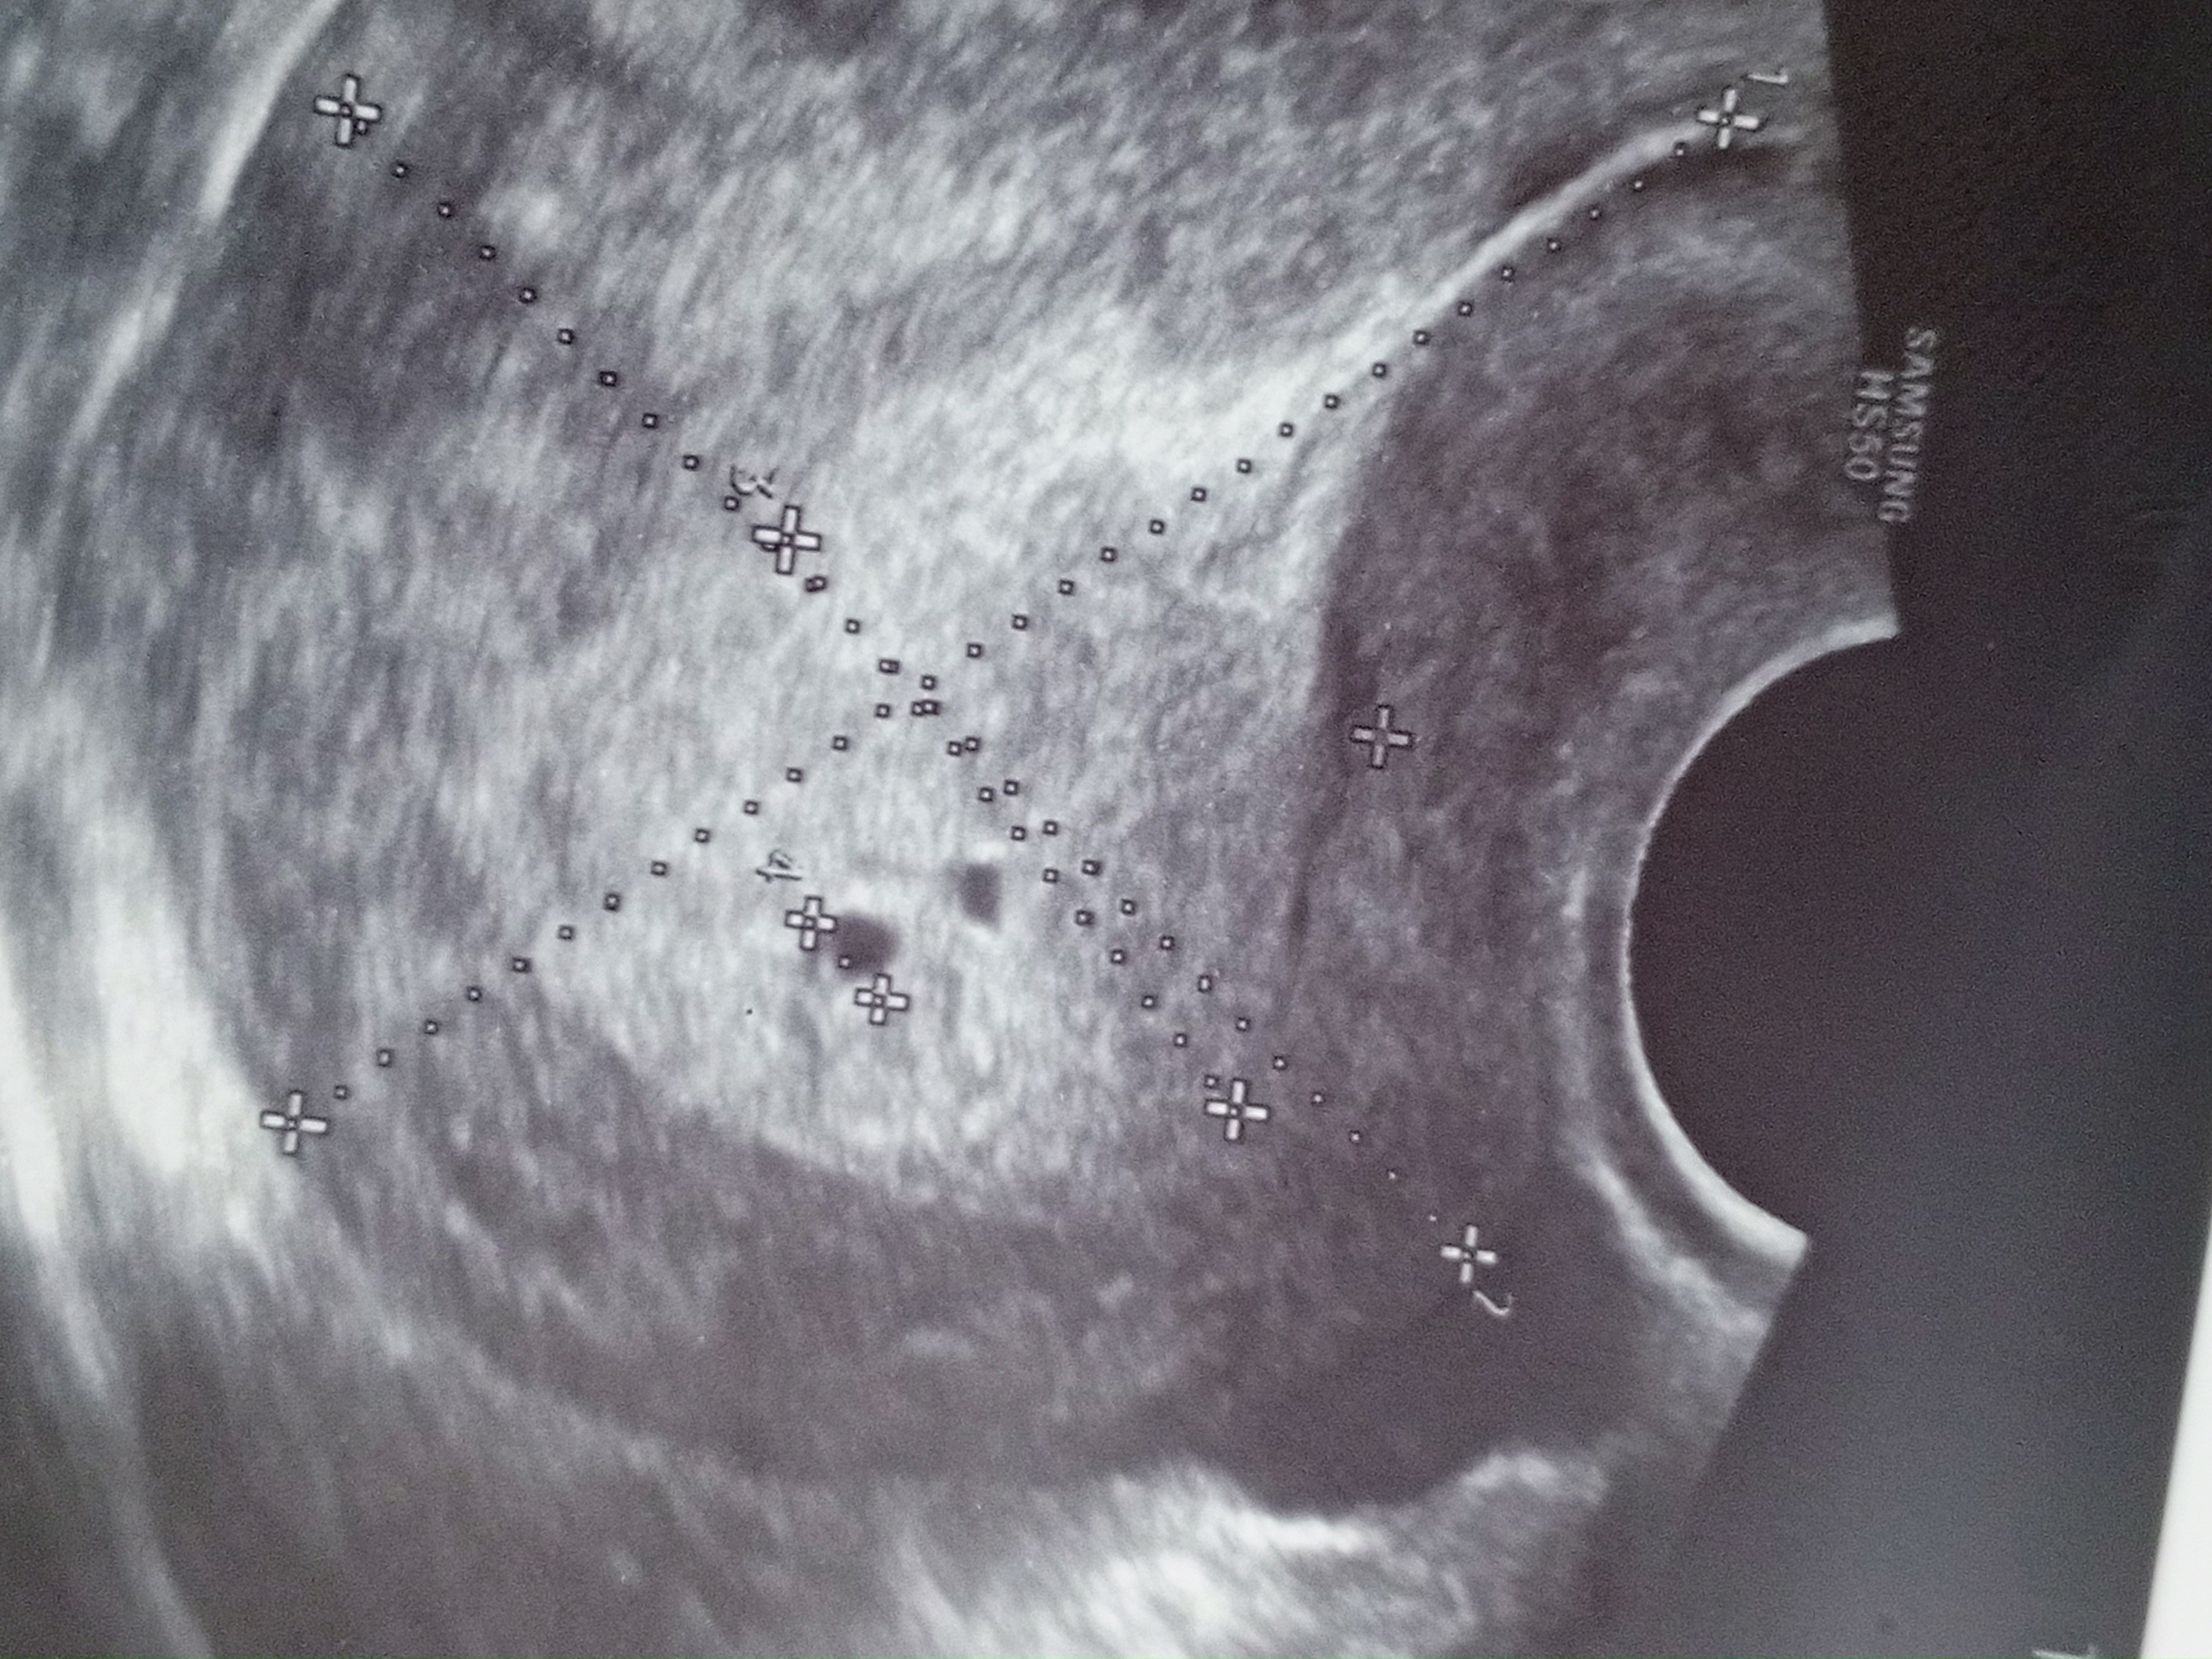

Роза, увидели что - то похожее на ПЯ ещё , но пока не уверенна говорит

У меня тоже подозрение на двойню но срок меньше наверно чем у вас, ходила в понедельник был 4.6 недель акушерских

Пока одно ПЯ, о двойни речь не идет. Дальше что угодно может произойти.

Пока у вас одно пя. Все